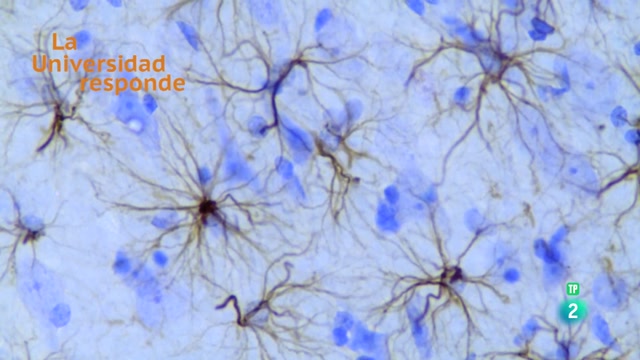

¿Qué son las células gliales? Universidad Autónoma Barcelona. La Universidad Responde.